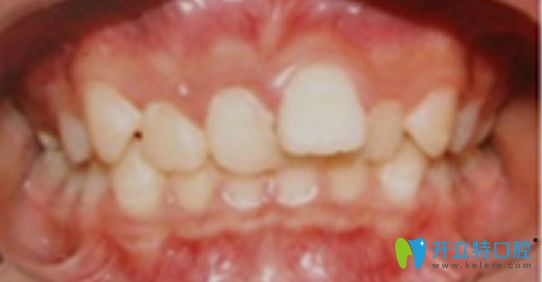

這是我孩子牙齒矯正前的照片:

常州太平洋口腔牙齒矯正前的照片